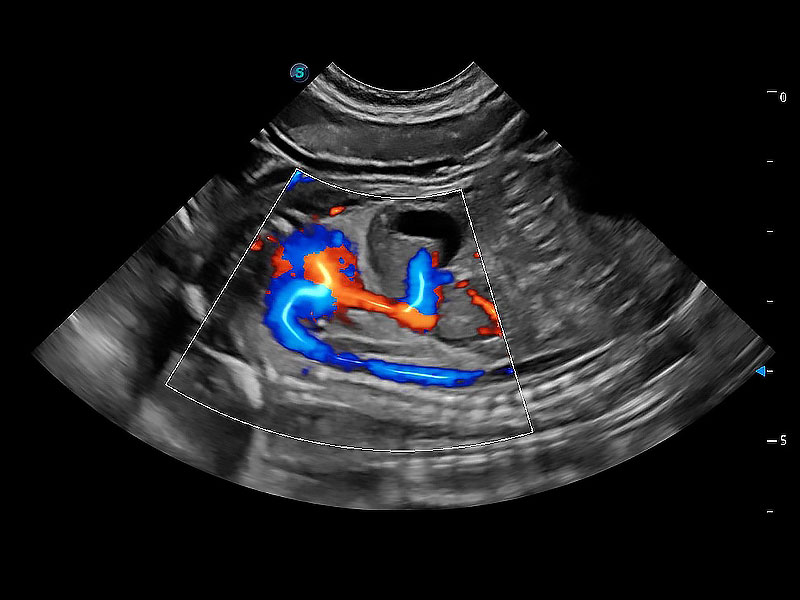

極大提升超低速微細(xì)血流的檢出能力,同時更精準(zhǔn)地濾除軟組織和超聲信號,為獸用醫(yī)生提供以往無法通過常規(guī)血流獲得的疾病診斷信息。

在傳統(tǒng)二維血流成像的基礎(chǔ)上,呈現(xiàn)血流的立體感,具有動感的生命力之美。即便是微小的血管也能輕松應(yīng)對,提高了血流的視覺敏感性。